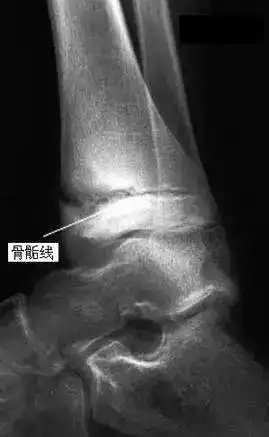

怎么看自己骨骼线是否.这是膝盖部位的X光图。左图中,标问号的地方看起来是2道缝,其 说明骨骺线已经接近闭合,这个时候骨骼的生长发育趋于缓慢。当你的骨骺线完全闭合以

病情分析: 最简单的方法就是去医院的骨科拍张膝关节x光片。看能不能长高,如果骨骺线清晰可见有继续长高的可能,中间透亮线已经和胫骨近端长在一起,基本不可能继续长高了。

如果是分离的有两条横白线的,就可以再长身高,否则就是骨垢闭合,吃什么药也不长。想知道骨骼是否闭合,建议患者可以先去医院拍一个X光片。一般来说骨骺线会随着年龄的增